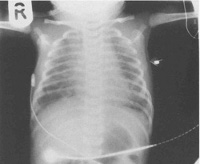

Синдром аспирации мекония. Состояние острой дыхательной недостаточности вследствие внутриутробного попадания в легкие ребенка мекониальных масс с закупоркой просвета бронхов. Характерен синюшный оттенок кожи с рождения, тяжелое шумное дыхание с западением уступчивых мест груди. Состояние расценивается как тяжелое. Синдром аспирации мекония диагностируется на основании внешних признаков дыхательной недостаточности, физикального осмотра и рентгенографической картины. Лечение комплексное, направлено на механическое очищение бронхиального дерева, усиленную оксигенацию и борьбу с инфекционными осложнениями.

Первичная диагностика возможна еще в процессе планового обследования во время беременности. Кардиотокография плода отчетливо показывает затруднение дыхания малыша, в подобных случаях необходимо дальнейшее обследование и поиск причин гипоксии, в частности – анализ амниотической жидкости для выявления в ней частиц мекония. Возможно решение вопроса о досрочном родоразрешении. В процессе интранатальной диагностики синдрома аспирации мекония обращает на себя внимание зеленоватый цвет околоплодных вод, иногда частицы мекония удается визуализировать. Также часто наблюдается зеленоватый цвет ногтей, кожи и пуповины малыша, что, как правило, свидетельствует в пользу длительной внутриутробной гипоксии и тяжелого течения синдрома аспирации мекония.

Важно учитывать, что к моменту подключения ИВЛ легкие должны быть очищены, поскольку в противном случае возможно продвижение оставшихся частиц мекония в дистальные отделы с последующим усугублением дыхательной недостаточности. С целью более быстрого расправления участков ателектаза назначается сурфактант, иногда – оксид азота. Обязательно применение антибиотиков, поскольку частым осложнением синдрома аспирации мекония является аспирационная пневмония. В наиболее тяжелых случаях выполняется экстракорпоральная мембранная оксигенация. Все манипуляции проводятся в отделении реанимации.